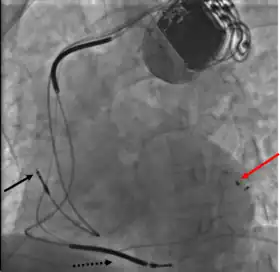

CRT devices have at least two leads, one passing through the vena cava and the right atrium into the right ventricle to stimulate the septum, and another passing through the vena cava and the right atrium and inserted through the coronary sinus to pace the epicardial wall of the left ventricle. Often, for patients in normal sinus rhythm, there is also a lead in the right atrium to facilitate synchrony with the atrial contraction. Thus, the timing between the atrial and ventricular contractions, as well as between the septal and lateral walls of the left ventricle can be adjusted to achieve optimal cardiac function.

Pacemaker lead malposition in various locations has been described in the literature. Treatment varies, depending on the location of the pacer lead and symptoms.[55]